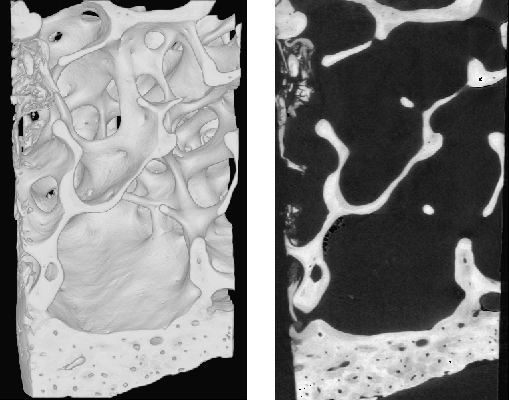

Fig. 138: Reconstructed image of iliac crest biopsy sample: 3D display (a) and first 2D slice (b). Voxel size = 10.13 µm. |

SR µCT images may be interpreted as accurate maps of the 3D distribution of the linear absorption coefficient within the volume. Since the absorption depends on the mineral content of bone, we employed a calibration method relating the reconstructed gray level to the degree of mineralisation (concentration of hydroxy apatite). The method was first compared to the reference microradiography technique. Then, it was applied to the analysis of human biopsies from osteoporotic patients before and after one and two years of bisphosphonate treatment (Figure 138). The distribution in concentration of hydroxyapatite evaluated from the biopsies of one patient, before and after one and two years of treatment is illustrated by Figure 139. The shift towards the right of the histogram after treatment indicates that the bone sample is more mineralised. While no significant changes regarding structural parameters were observed with treatment, the statistical analysis exhibited a positive trend towards higher mineralisation. Thus, SR µCT appears as a unique tool for analysing bone samples both in terms of microarchitecture and bone mineral content.